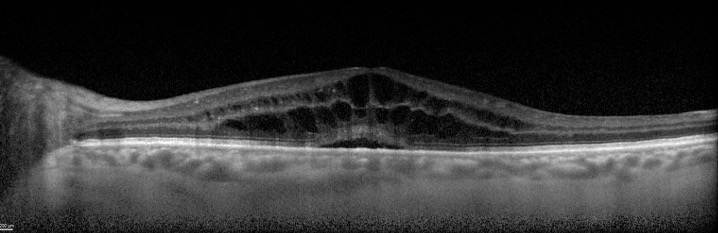

Cystoid macular edema (CME) is a condition that involves the accumulation of fluid within the layers of the macula, the central part of the retina that provides fine, detailed vision. CME can reduce central vision and impacts critical fine visual tasks such as reading.